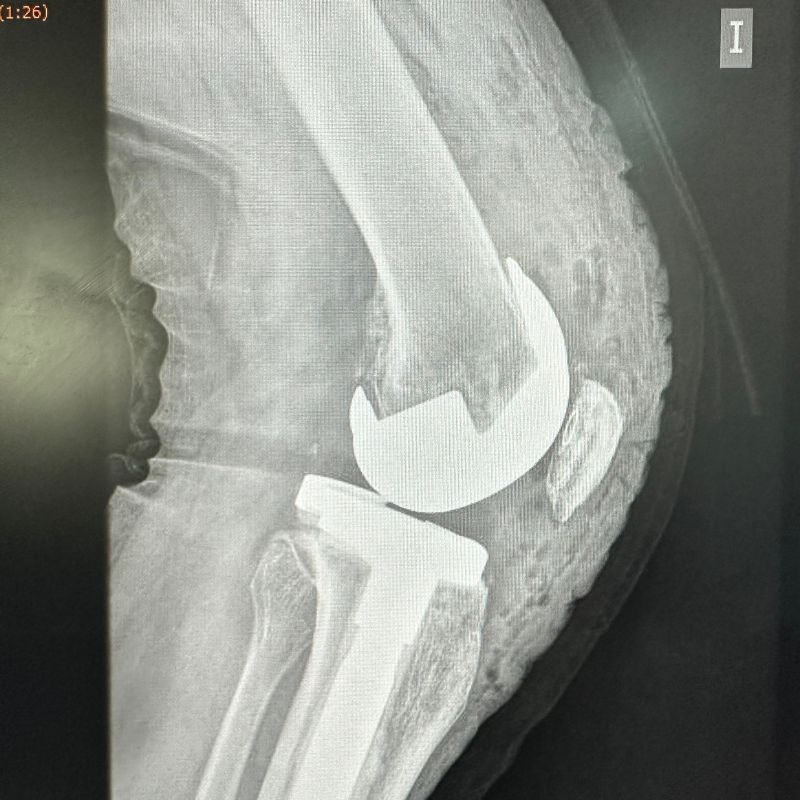

- Prótesis unicompartimentales de Rodilla.

- Prótesis Total de Rodilla.

- Retiro de Prótesis de Rodilla dolorosa o fallida.

- Prótesis de Revisión de Rodilla.